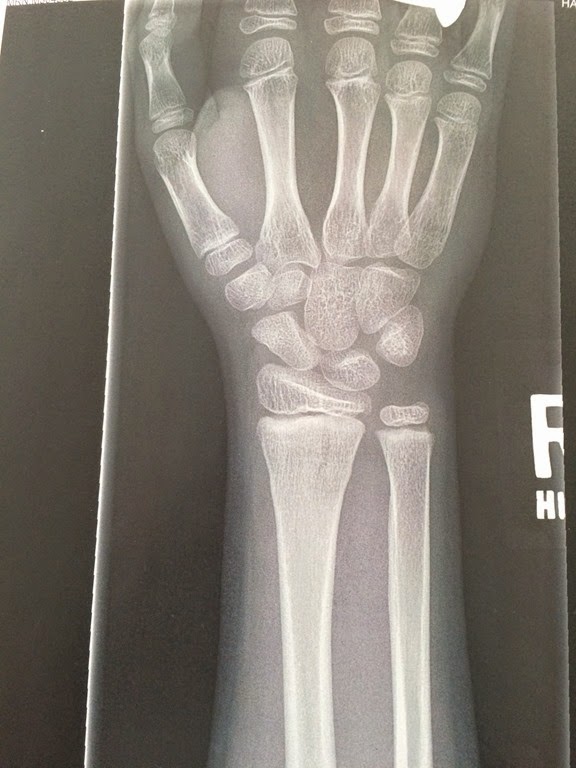

Notice where the radius bone (big arm bone to the left) bulges out slightly on both sides.

I drew lines to show where the true line of the bone should be.  That slight bulge or buckle was the proof apparently.

Verdict: Broken!  The technical term is “distal radius buckle fracture”.  Rock’s cousin helped us understand why we couldn’t tell it was broken by looking at this x-ray.  He said your bone is like a stick with a bunch of saran wrap around it.  If the stick breaks, the saran wrap holds it together if it’s not too big of a break.  And the “saran wrap” is pretty strong when you’re a kid.  That’s why it is so hard to see the actual break.